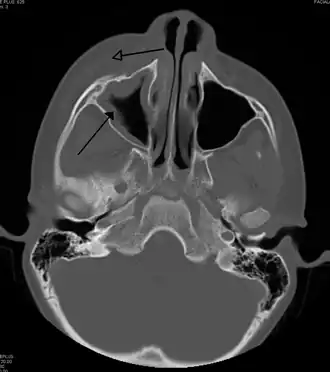

| Periorbital cellulitis caused by a dental infection (also causing maxillary sinusitis) | |

Periorbital cellulitis, or preseptal cellulitis, is an inflammation and infection of the eyelid and portions of skin around the eye anterior to the orbital septum.[1] It may be caused by breaks in the skin around the eye, and subsequent spread to the eyelid; infection of the sinuses around the nose (sinusitis); or from spread of an infection elsewhere through the blood.

Periorbital cellulitis must be differentiated from orbital cellulitis, which is an emergency and requires intravenous (IV) antibiotics. In contrast to orbital cellulitis, patients with periorbital cellulitis do not have bulging of the eye (proptosis), limited eye movement (ophthalmoplegia), pain on eye movement, or loss of vision. If any of these features is present, one must assume that the patient has orbital cellulitis and begin treatment with IV antibiotics. CT scan may be done to delineate the extension of the infection.

Tests include blood work (CBC) to rule out infectious cause. Also perform a CT scan, x ray of the anterior skull to view the sinuses, MRI scan and finally a soft tissue ultrasound of the orbital region.